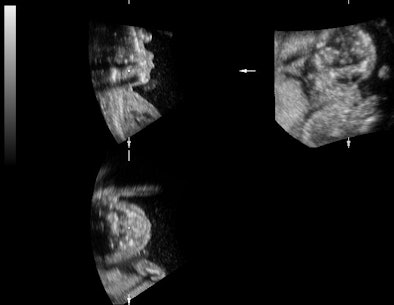

![]() |

| Representative fetal profile images showing good-quality (above), acceptable-quality (below), and poor-quality (bottom) images. All images courtesy of the Journal of Ultrasound in Medicine. |